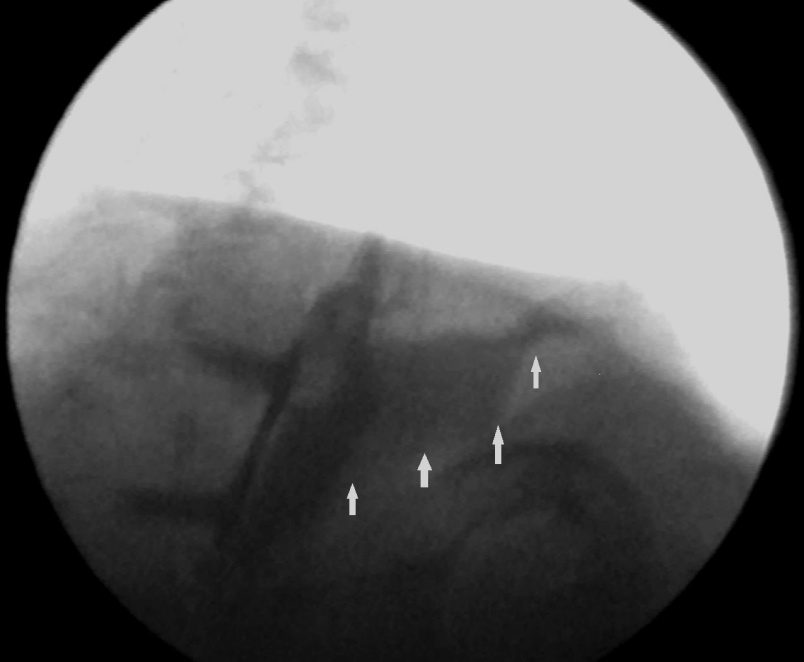

Yellow arrow — Thick-walled gallbladder with gallstones. Blue arrow — Stomach segment. Light blue arrows — Cholecystogastric fistula (Courtesy Dr. V. Penopoulos)